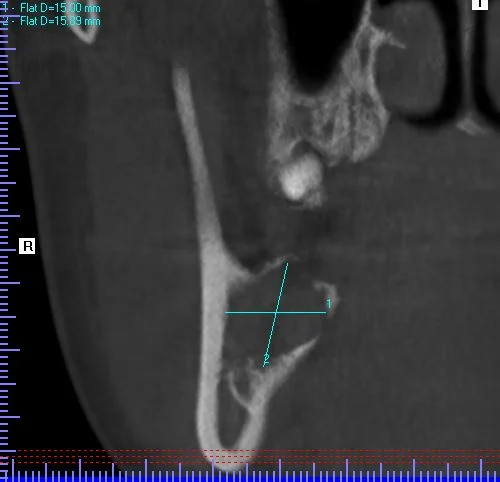

A 20-year-old male presented to our facility with a referral for a painful radiolucency of the right posterior mandible. Other than a two-year history of tobacco use, his past medical and surgical histories were unremarkable. On clinical exam, there were no mucosal changes, no palpable buccal or lingual swelling, and tooth #29, #30, #31 tested vital with no mobility, probing depths distal to #31 measured 7-8mm. On CBCT examination, the lesion exhibited a well-circumscribed, regular bordered radiolucency approximately 25mmx18mm in its greatest dimension in the right posterior mandible directly adjacent to #31. The lingual cortical plate was violated, however, the roots of tooth #31 remained intact. Additionally, the inferior pole of the lesion was contiguous with the superior aspect of the Inferior Alveolar nerve canal, but did not displace the nerve/canal (Figure 1). Tooth #32 was missing and, per patient report, had never developed. Differential diagnosis based on location and demographics included Dentigerous Cyst, Odontogenic Keratocyst, Ameloblastoma, Myxoma and Hemangioma in order of most to least likely diagnosis. After the risks, benefits and alternatives were discussed with the patient, he elected to undergo excisional biopsy under IV General Anesthesia.